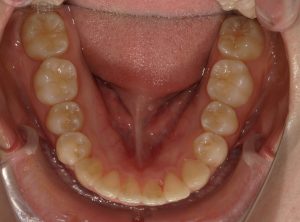

治療前→治療後(下顎)

親知らずを抜き、下のガタガタを改善しました。